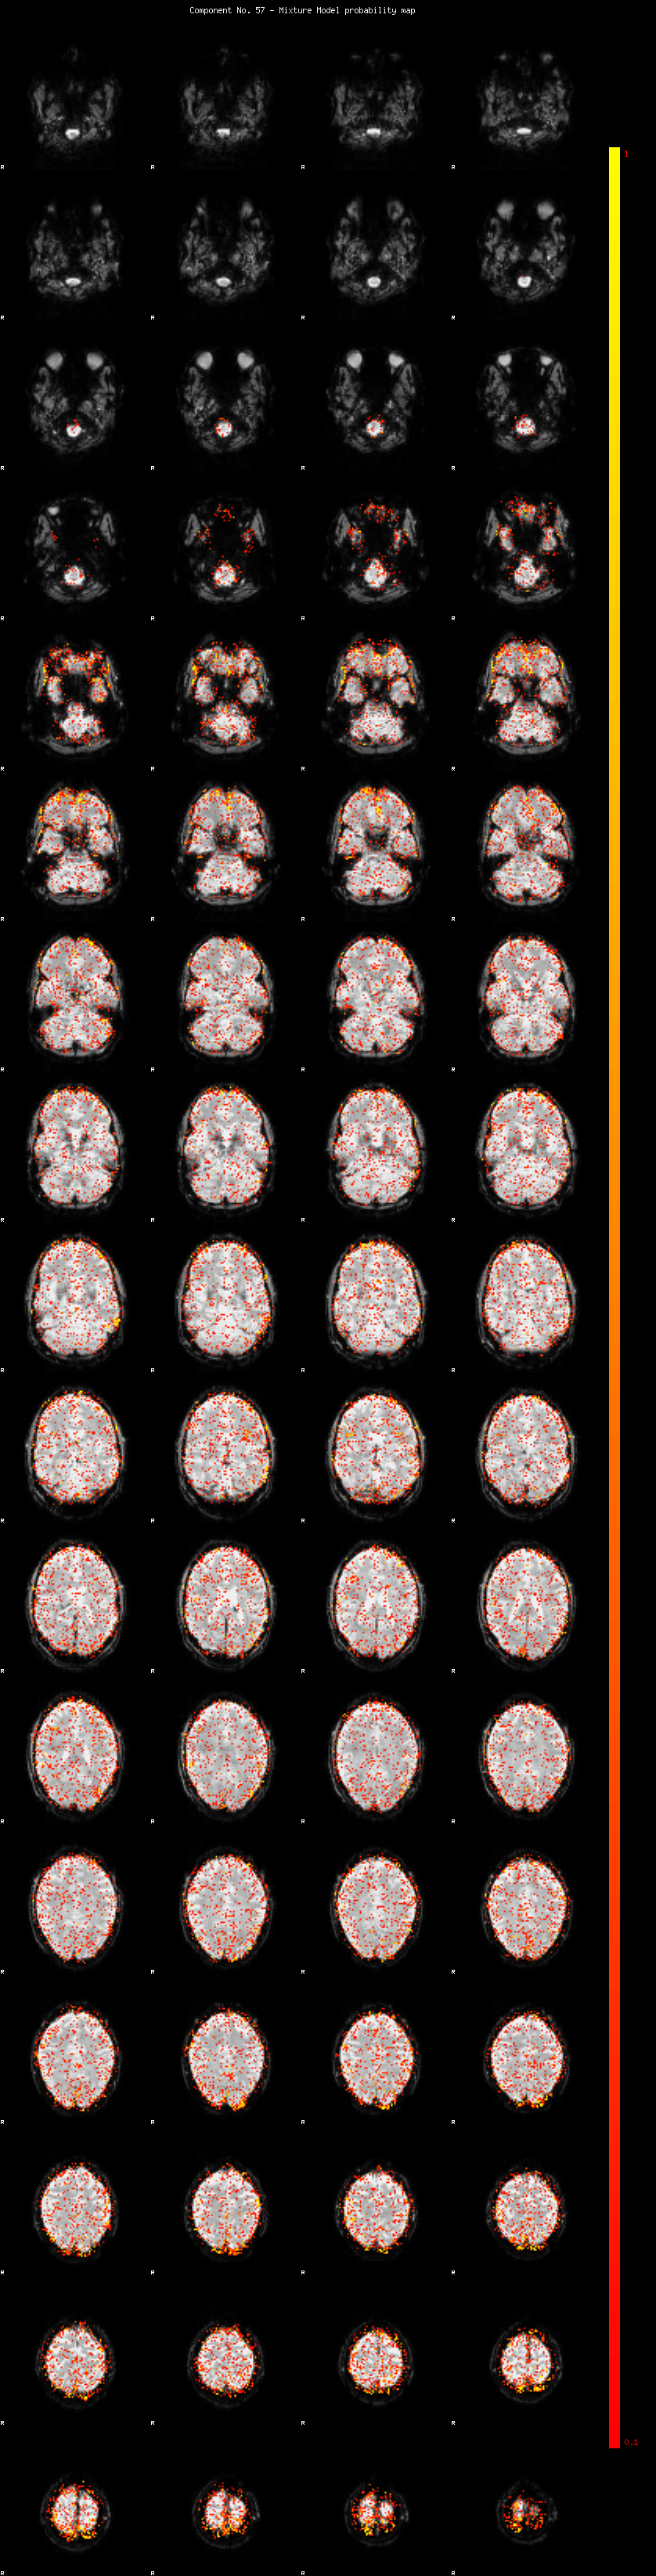

IC_57 Mixture Model fit

Means : -0.000000 2.238712 -2.177601

Vars : 1.000000 1.282181 1.123885

Prop. : 0.936753 0.033046 0.030200